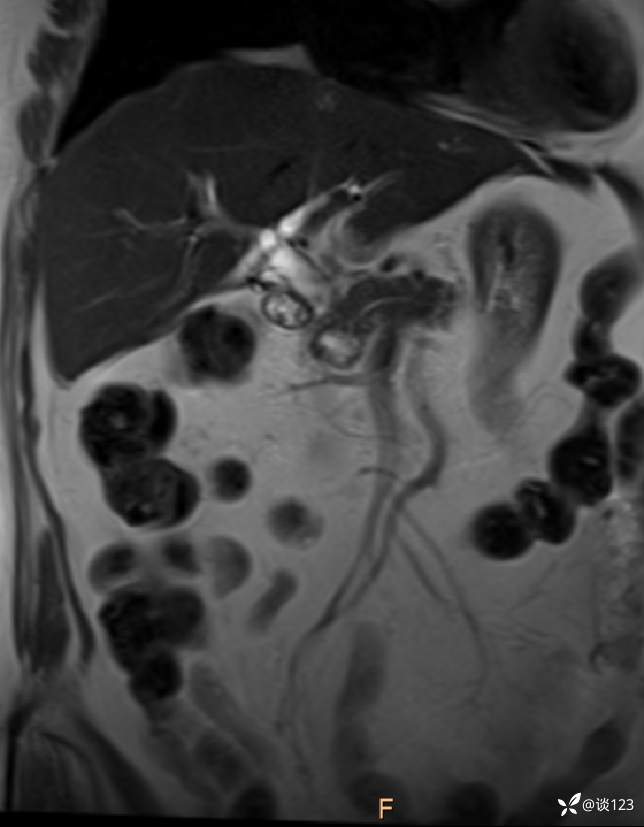

再做MRI

cor T2WI

DWI